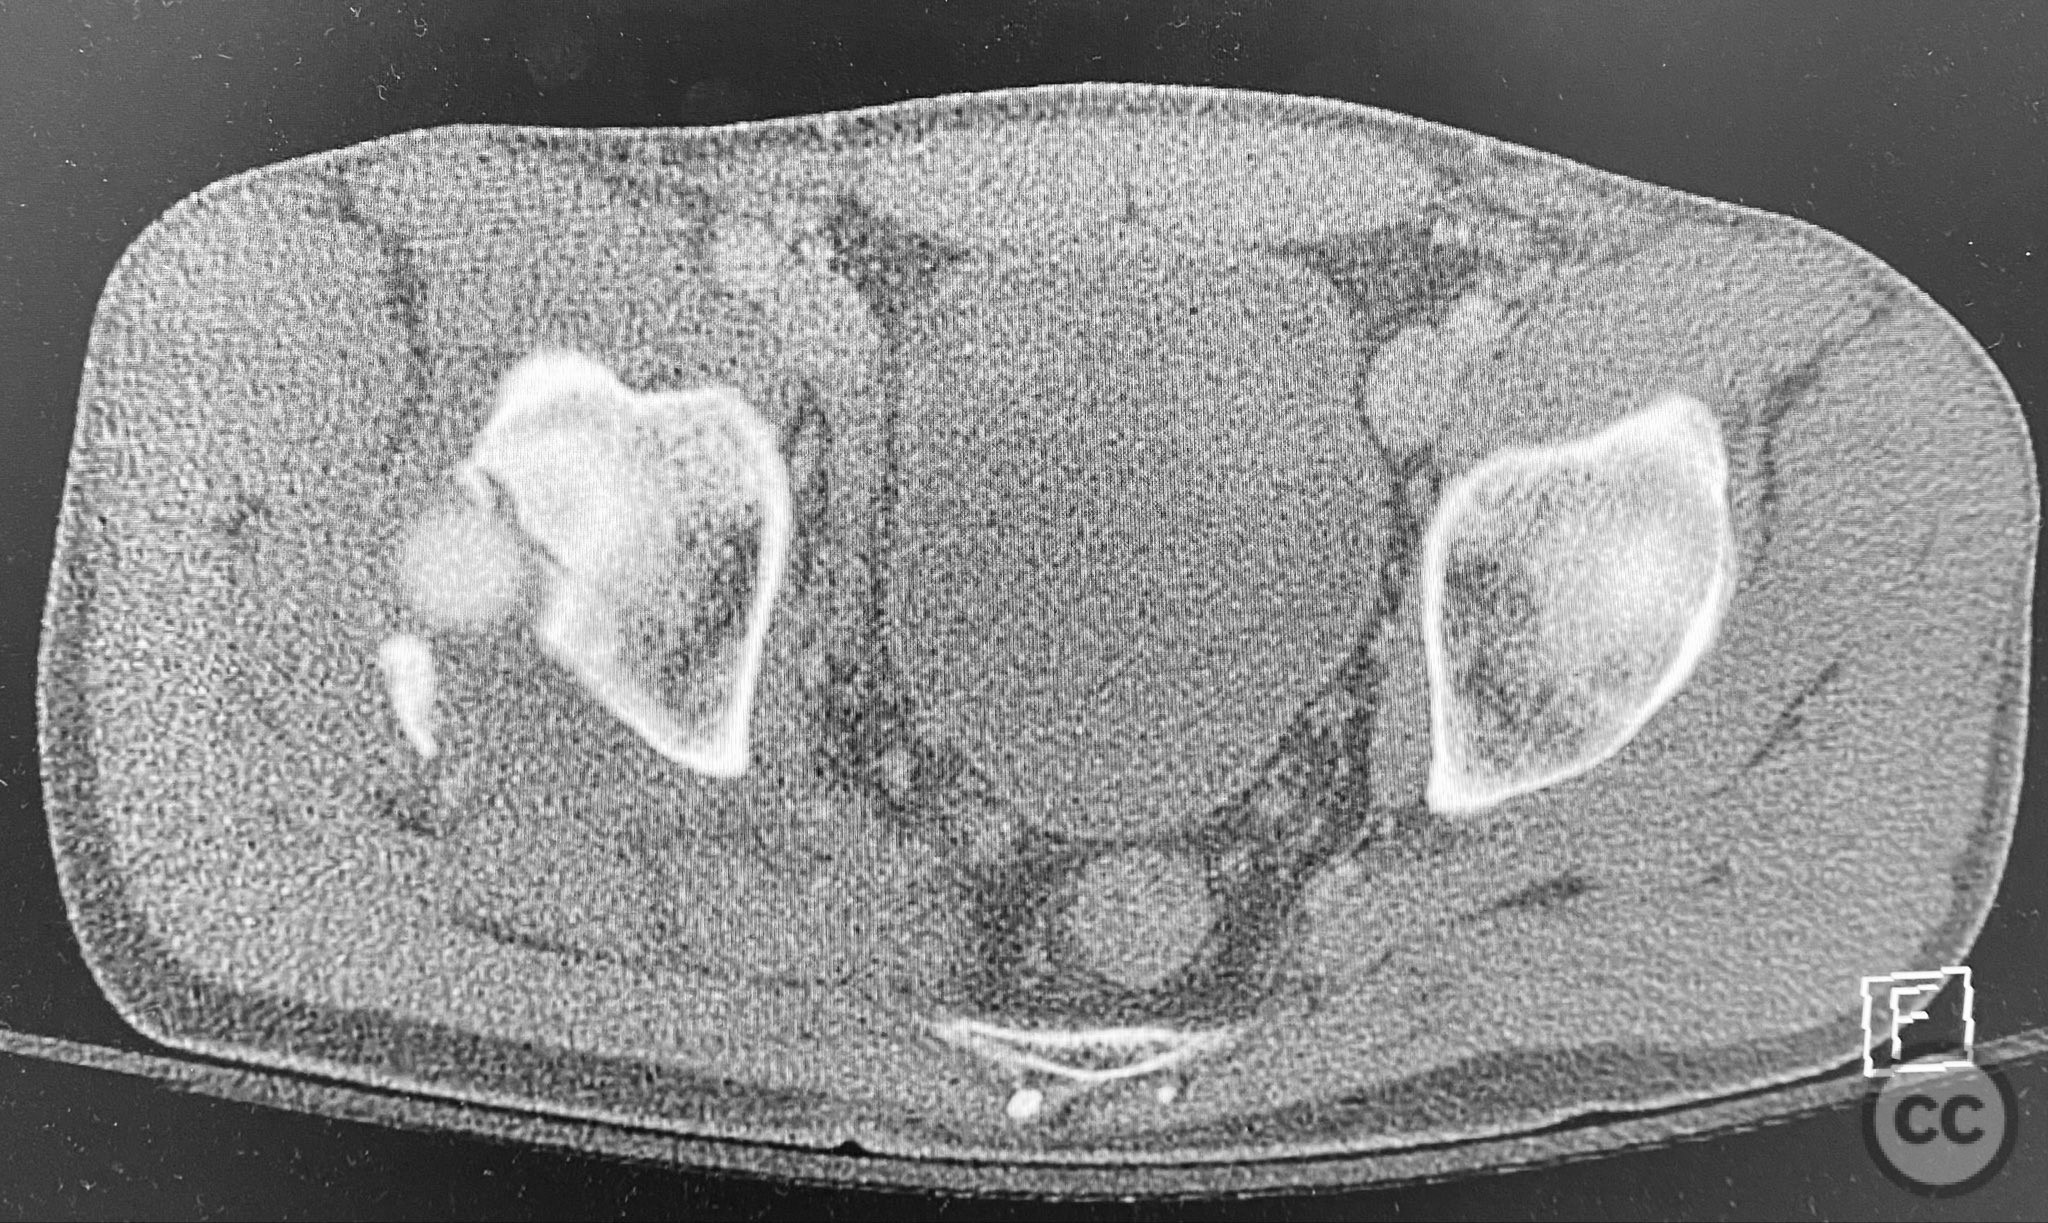

Clinical and radiological findings:  A middle-aged patient sustained a posterior wall acetabular fracture-dislocation, as demonstrated on initial AP pelvic radiograph. The film revealed a sizeable posterior wall fragment, cranial lateral impaction of the acetabular dome, and subtle deformation of the femoral head contour. Neurovascular examination was performed, including assessment of distal pulses and sciatic nerve function. The ipsilateral knee and anterior chest were examined for associated injuries (including possible knee ligamentous injury and thoracic trauma). An initial attempt at closed reduction under sedation was unsuccessful.

Planning remarks:  The preoperative plan included advanced imaging with CT, including 3D surface renderings, to further delineate the extent of articular impaction, wall fragment size, and comminution. The plan was for open reduction and internal fixation via a posterior Kocher-Langenbeck approach in the prone position. Elevation of impacted articular segments was planned, with structural support using autologous bone graft harvested from the greater trochanter. Fragment-specific fixation was planned with a spring hook plate for the cranial wall fragment and a reconstruction plate for the main posterior wall fragment.